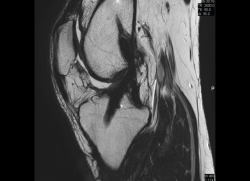

4. Lesiones isquémicas

4.1. Necrosis avascular (NAV)

En la NAV (aséptica, isquémica u osteonecrosis), hay una pérdida del flujo de sangre en el tejido óseo que hace que el hueso muera.

Se produce por un trastorno de la irrigación sanguínea o por lesiones celulares en el hueso y en la médula ósea.

Puede observarse en la RM la disminución de la intensidad de la lesión mucho antes de que se aprecie con otras pruebas diagnósticas (Figura 51).

4.2. Infartos

Los infartos medulares óseos aparecen en el 0,06% de los pacientes a quienes se les ha realizado una RM del aparato locomotor. Se presentan como lesiones segmentarias, puramente medulares, sin afección cortical, normalmente múltiples y que afectan predominantemente a los huesos largos de las extremidades, sobre todo las inferiores. La RM es esencial en el diagnóstico por imagen, apareciendo como lesiones óseas intramedulares de contornos serpiginosos hipo- o isointensos en secuencias T1 e hiperintensos en T2. Por tanto, la RM es el instrumento crucial en las fases iniciales, ya que permite caracterizar las lesiones y proceder a su diagnóstico temprano(19)(Figura 52).